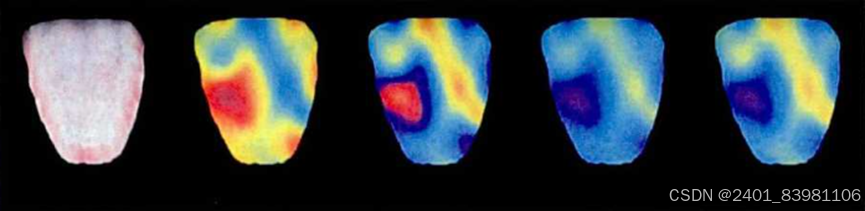

采用VGGNET,GradCAM(可以对任意结构的CNN进行可视化),基于创新h-Net模型的中医舌苔苔质分类及其舌苔特征可视化,基于高光谱图像的中医舌苔和舌质分类等

采用VGG时网络优化过程中应用了Dropout策略网络优化策避免过拟合问题但训练样本较少,采集数据困难,训练样本包含舌头外的无关区域等原因,产生的可视化效果并不够完美,仍具有相当大的改进空间

对应的可视化图:

采用h-Unet解决Unet没有全连接层问题(对应可视化图)

采用VGG时网络优化过程中应用了Dropout策略网络优化策避免过拟合问题但训练样本较少,采集数据困难,训练样本包含舌头外的无关区域等原因,产生的可视化效果并不够完美,仍具有相当大的改进空间